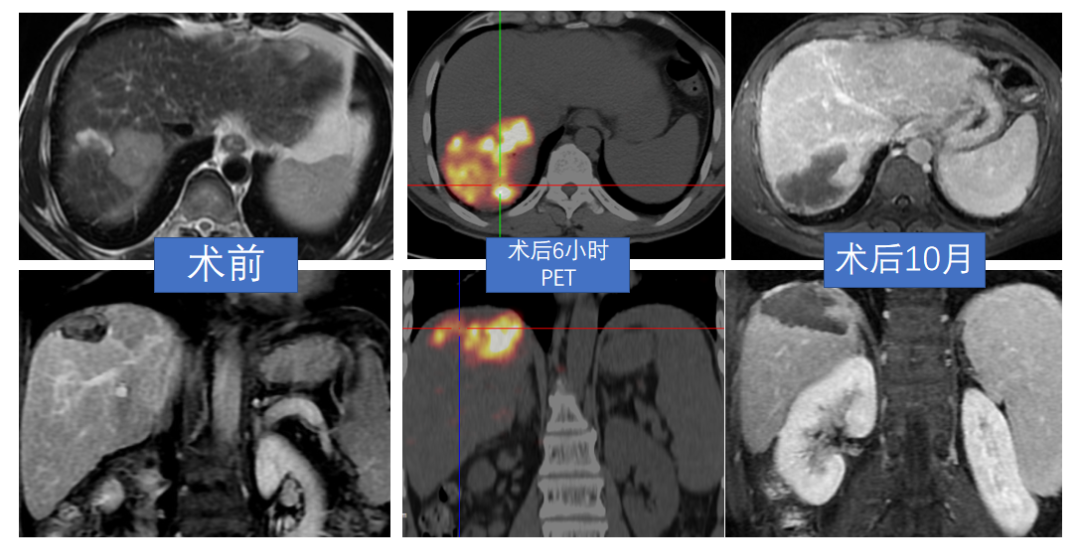

大陆第一例放射性切肝段切除

患者肝7段2.5x1.8x1.5cm肿块,行S7肿瘤+胆囊切除,病理报HCC、有微脉管侵犯,1年后复查:AFP:10021.9ng/ml,右肝S8见4.0cm肿块。

术后10个月复查,肿瘤全坏死,患者未出现任何治疗相关副反应。该案例表明,Y90微球放射性肝段切除治疗HCC安全有效。

连续随访24个月肿瘤完全坏死,肿瘤标志物正常。